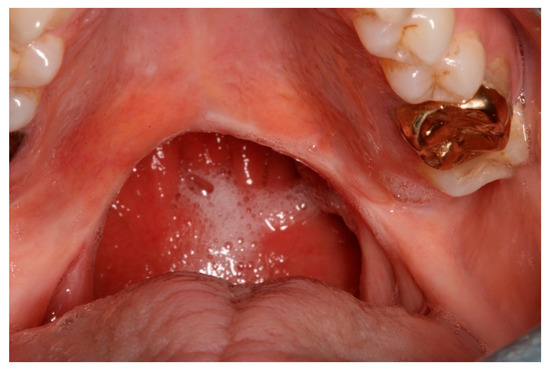

CH was diagnosed with an adenoid cystic carcinoma of her soft palate in 2012 and underwent a wide local excision under general anaesthesia. The extent of the surgical excision of the soft palate can be seen in Figure 1.

Figure 1. Intra-oral view showing the healed tissues following wide surgical excision of the soft palate.